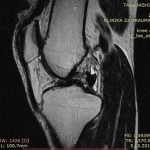

Pročitajte više →Rekonstrukcijska operacija koljena

Evo! Od 25.7. do 18.8. sam na godišnjem odmoru. U to vrijeme ću ići na rekonstrukcijsku operaciju lijevog koljena ACL(prednji križni ligament) da ozljeda se dogodila tijekom Judo treningana, kirurg će biti prof.dr.sc Saša Janković, dr.med u Sv. Duhu. Oporavit ću se i vratiti na posao što je prije moguće, radiim kao Japanac!